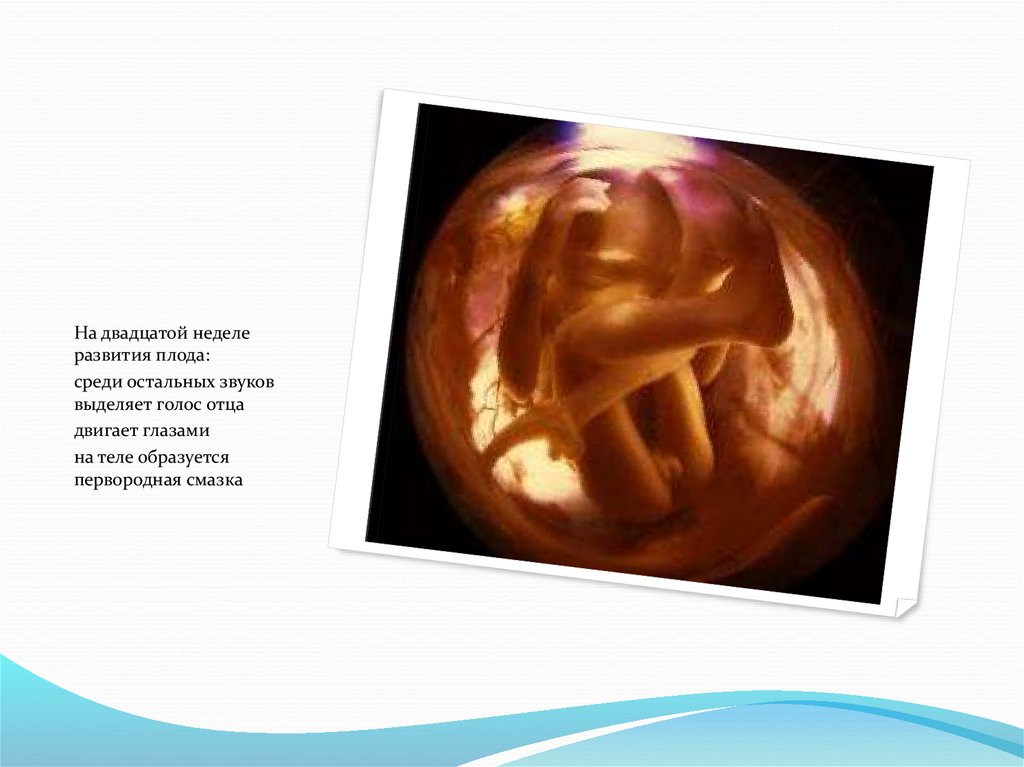

Важный этап: развитие малыша на 20-й неделе беременности

Раздел: Снимки-откровения